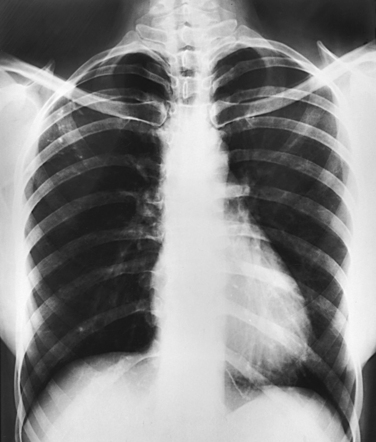

The position of the diaphragm varies with body habitus: It is at a higher level in hypersthenic patients and at a lower level in asthenic patients (Fig. 9-9). In sthenic patients of average size and shape, the right side of the diaphragm arches posteriorly from the level of about the 6th or 7th costal cartilage to the level of the 9th or 10th thoracic vertebra when the body is in the upright position. The left side of the diaphragm lies at a slightly lower level. Because of the oblique location of the ribs and the diaphragm, several pairs of ribs appear on radiographs to lie partly above and partly below the diaphragm.

Fig. 9-9 Diaphragm position and body habitus. A, A hypersthenic patient has a diaphragm positioned higher. B, An asthenic patient has a diaphragm positioned lower. C, Chest radiograph of a hypersthenic patient. D, Chest radiograph of an asthenic patient. Note position of diaphragm on these extremely different body types.